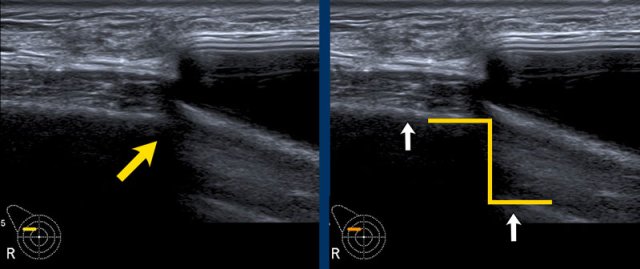

Normal findings

Inverted Oreo sign

The envelope of the prosthesis can be seen as an inverted Oreo cookie. The first white line is the outer interface of the envelope and the second white line is the inner interface between the envelope and the Silicone gel (yellow arrow).

In between the outer layer of the envelope and the surrounding capsule there is a virtual space that can fill and broaden.

The capsule is seen apart from the envelope as a separate white line anterior to the envelope (white arrow).

Envelope and capsule together are called envelope-capsule complex.

Step off sign

The step off sign is an artefact caused by a lower transmission speed of the ultrasound waves through Silicone ( 970m/sec in Silicone gel and 1540m/sec through water).

As a result the chest wall seems to be deeper at the level of the prosthesis.

This artefact is not seen in saline filled implants.